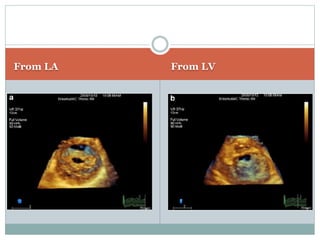

3D ECHO

 TEE and TTE

 Higher accuracy than 2D echo

 Detailed information of commissural fusion and

subvalvular involvement

 MVA measurement in calcified and irregular valve

 MVA measurement after BMV

 Restenosis after commissurotomy

commissural refusion

valve rigidity with persistent commissural opening

From LA From LV